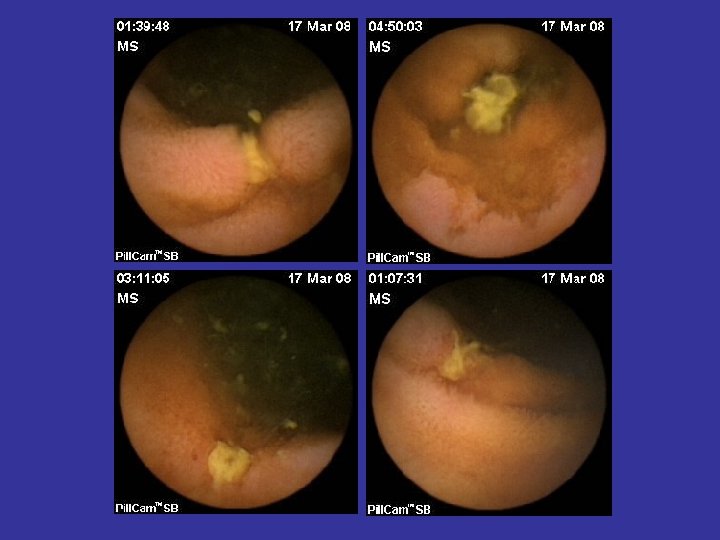

Hemoragia digestiva de cauza obscura (OGIB) • Indicatia majora a WCE • Acuratete diagnostica superioara (~ dubla) tuturor celorlalte metode diagnostice (Rx, PE, DBE, etc) • Administrare cat mai precoce dupa episodul hemoragic (< 48 ore) • WCE: rol in orientarea managementului si ameliorarea prognosticului • Repetarea WCE dupa un examen negativ creste acuratetea diagnostica

Tipuri de leziuni depistate in BC • • Eroziuni Edem mucosal Congestie parcelara Ulceratii aftoide; Ulcere liniare/ neregulate/ confluente; Pseudopolipi inflamatori; Stenoze inflamatorii;